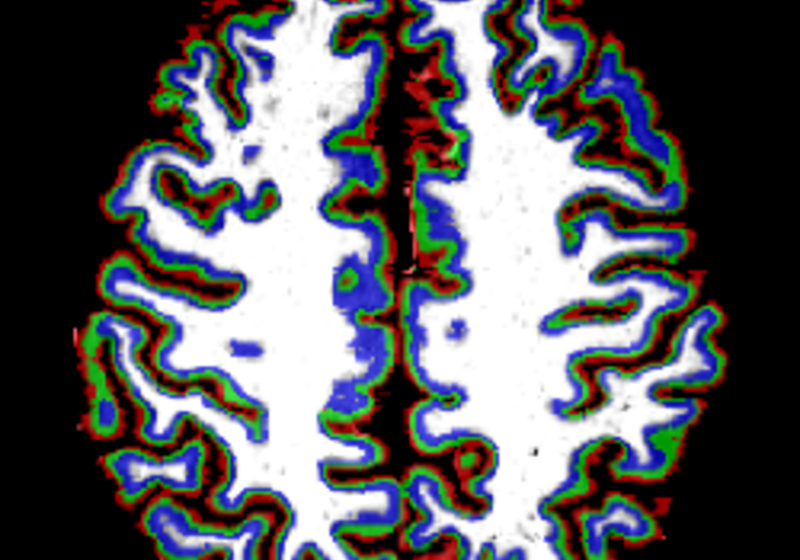

We have a position available for a post-doctoral Research Associate position in Neuroimaging and Neurocomputation The position will focus on neuroimaging and neurocomputational studies of learning and brain plasticity. Our studies combine ultra-high field brain imaging (7T fMRI, MR Spectroscopy), electrophysiology (EEG)...